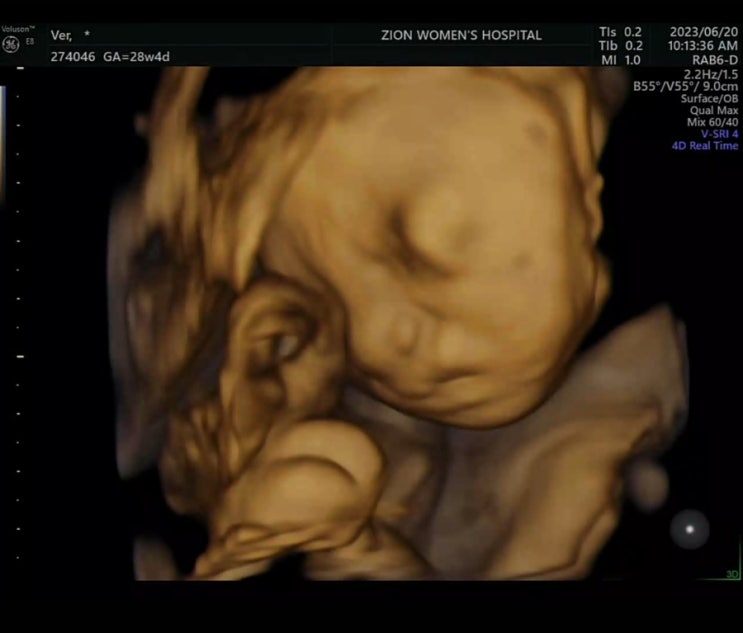

[ 임신기록 ] 28주차 입체초음파 보고왔어요 : 도치맘예약!